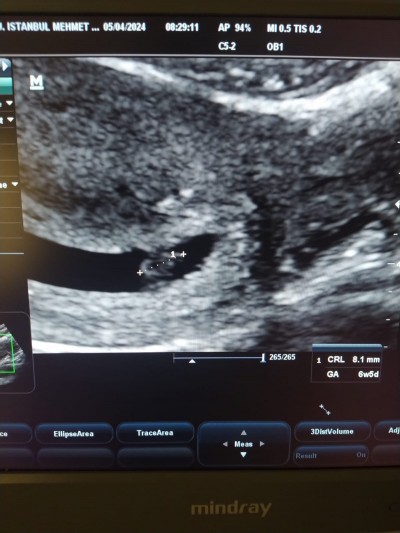

Arkadaşlar doktor ikiz veya tekil gebelik diye bilgilendirme yapmadı ama resme bakınca iki ayrı kese ve keselerin içinde beyaz nokta var gibi. Gazım veya idrarım okdupundan keselerin şekli ince gibi geldi bana. Sizcede iki ayrı kese ve iki ayrı bebek yok mu? Resmi ekliyorum

Diğer alan gebelik kesesi değil, rahim dışı dokuların olduğu bi alan. Tek gebelik gibi duruyor.